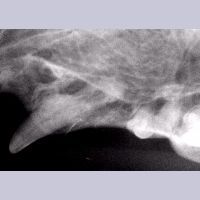

Image 7.6. Class 5 FORL의 뢴트겐 사진

Crown의 뿌리가 살아남음